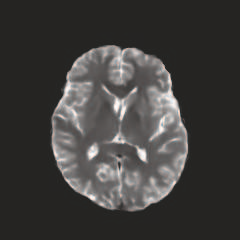

Multi-modal medical image completion has been extensively applied to alleviate the missing modality issue in a wealth of multi-modal diagnostic tasks. However, for most existing synthesis methods, their inferences of missing modalities can collapse into a deterministic mapping from the available ones, ignoring the uncertainties inherent in the cross-modal relationships. Here, we propose the Unified Multi-Modal Conditional Score-based Generative Model (UMM-CSGM) to take advantage of Score-based Generative Model (SGM) in modeling and stochastically sampling a target probability distribution, and further extend SGM to cross-modal conditional synthesis for various missing-modality configurations in a unified framework. Specifically, UMM-CSGM employs a novel multi-in multi-out Conditional Score Network (mm-CSN) to learn a comprehensive set of cross-modal conditional distributions via conditional diffusion and reverse generation in the complete modality space. In this way, the generation process can be accurately conditioned by all available information, and can fit all possible configurations of missing modalities in a single network. Experiments on BraTS19 dataset show that the UMM-CSGM can more reliably synthesize the heterogeneous enhancement and irregular area in tumor-induced lesions for any missing modalities.